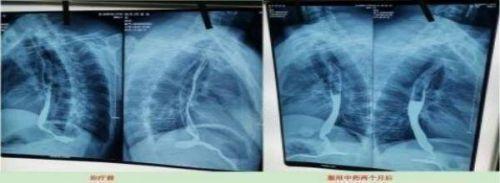

案例5、食道癌两个月清零

Case 5. Oesophageal cancer was cleared for two months

患者:刘喜良 男 46岁 食道中段癌

2023年10月9日CT影响报告诊断查出食管壁增厚,管腔狭窄,食管癌。找到陈海林老师使用中医药两个月治疗后CT显示食管各段顺利通过,食管恶性肿瘤治疗后改变。

Patient: Liu Xiliang, male, 46-year-old middle-esophageal cancer On 9 October 2023, CT affected the diagnosis of food tube wall thickening, lumen stenosis, and esophageal cancer. After finding Chen Hailin for two months, CT treatment showed the smooth passage of all section of the esophagus, and the esophagus of malignant tumor changed after treatment.

上图是服用两个月中药的前后对比图

Above is a comparison of before and after taking traditional Chinese medicine for two months